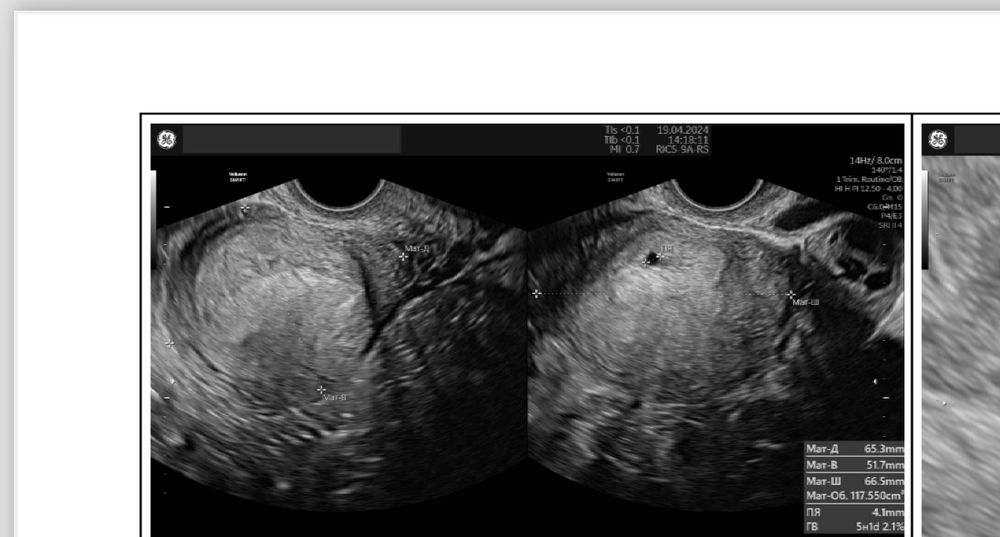

Я конечно до сих пор не могу понять как так получилось…Неделю назад нашли плодное яйцо в матке ,где уже был и желточный мешок и ктр…Вчера утром начались резкие боли до потери сознания..Сразу же на скорой отправили в больницу ,сделали узи и экстренно прооперировали..Лопнула труба,началось внутреннее кровотечение ,на момент операции давление было 70/40, и я потеряла более двух литров крови ..Сейчас в реанимации ((Ну как так ,а как же прошлое узи (((